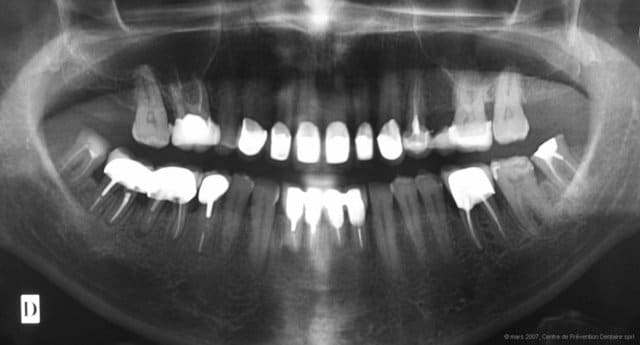

Pour le reste, voici la PANO « ETAT ANTERIEUR » du cas. Point essentiel à remarquer : multiples meulages « sélectifs » mettant à plat les cuspides des dents naturelles et/ou restaurations iatrogènes des surfaces triturantes. Ceci signe OBJECTIVEMENT une perte de la DVO ORIGINELLE, à laquelle s’ajoute le MANQUE d’ERUPTION des dents définitives, lié à la persistance, chez l’adulte, de la Déglutition Salivaire Infantile ou DS Atypique ou DS Dysfonctionnelle (voir "REIOR & GAL").